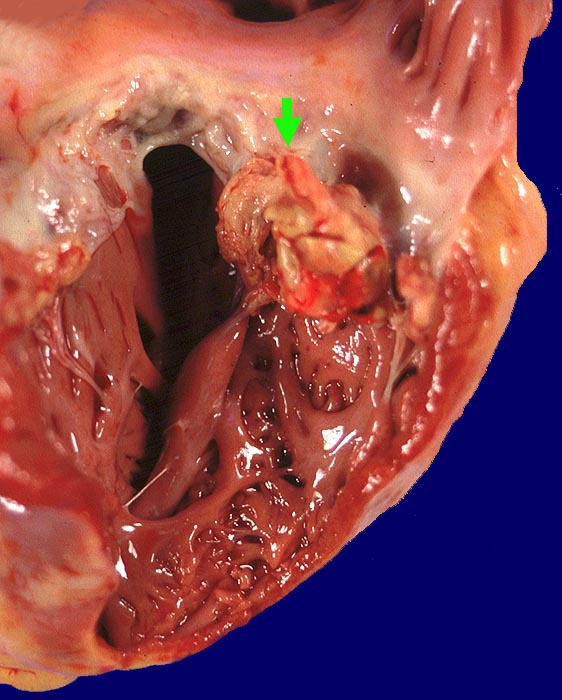

Basel 1MA/ Infektiöse Endocarditis ulcero-polyposa

Infektiöse Endocarditis ulcero-polyposa

Mitralklappe

Makroskopisch sind entweder flache rötliche fibrinbelegte Ulzera (=ulcerosa (> 2935)) oder zusätzlich weiche gelbbraune bröcklige erbs- bis pflaumengrosse Polypen (=ulceropolyposa (> 2936) (> 8376)) oder ausschliesslich polypoide Fibrinbeläge (=marantica) auf einem Endokarddefekt oder einer partiell zerstörten Klappe erkennbar.

Histologisch findet sich bei ulzeropolypöser Endokarditis ein Fibrin-Thrombozytenthrombus, welcher von Bakterien durchsetzt ist (=Vegetation). Die Vegetation sitzt auf einem Klappendefekt an dessen Basis Granulationsgewebe einzusprossen beginnt, welches den Thrombus organisiert. Klappendefekte, Gefässeinsprossungen, verdickte Sehnenfäden (> 2848) oder Kommissurenverwachsungen (> 8389) der Taschenklappen weisen morphologisch auf eine abgeheilte Endokarditis hin.